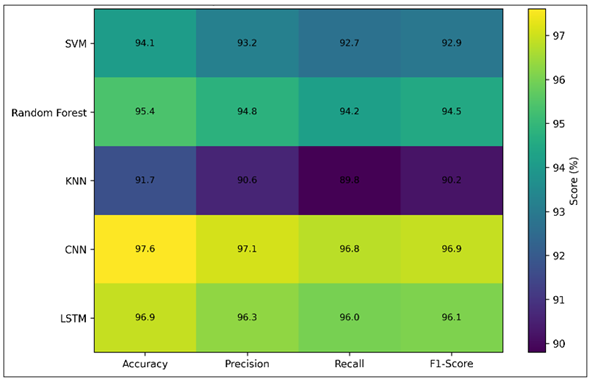

The proposed machine learning framework can be effectively used to identify cardiac abnormalities in ECG signals as demonstrated by the experimental evaluation. The standard performance metrics applied to evaluate the classification models were accuracy, precision, recall, and F1-score. The metrics present full information of the ability of the system to differentiate normal heart beats and abnormal conditions like arrhythmias. Dependable performance analysis is essential to test automated diagnostic systems since the incorrect diagnosis of abnormal heart conditions can be devastating to patients. Thus, several algorithms were compared in order to find out which model offers the most reasonable compromise between the detection rates and the computational efficiency. The relative effectiveness of the deployed machine learning models is depicted in Figure 3 that displays a bar chart in groups demonstrating the accuracy, precision, recall, and F1-score of all classification algorithms. Deep learning architectures proved to be better than the other models that were analyzed. The Convolutional Neural Network obtained the best accuracy of 97.6, the Long Short-Term Memory network is next with a 96.9 accuracy. Other traditional machine learning models like Support Vector Machines and random forest classifiers also yielded good results with a higher accuracy of above 94 and K-Nearest Neighbor model yielded lower results because it is sensitive to features scaling and ECG noise.

To continue to discuss the usefulness of the classification algorithms, a heatmap representation of performance metrics was created, and it is depicted in Figure 4. Heatmap visualizations enable the researcher to be able to quickly find trends among various metrics of evaluation. The visualization demonstrates the stable performance edge of deep learning models in all the parameters of evaluation. The models (CNN and LSTM) are more precise and have a higher recall than the traditional machine learning methods, which implies that it can detect abnormal ECGs and reduce false positives.

Figure 4 Heatmap Representation of Model Evaluation Metrics